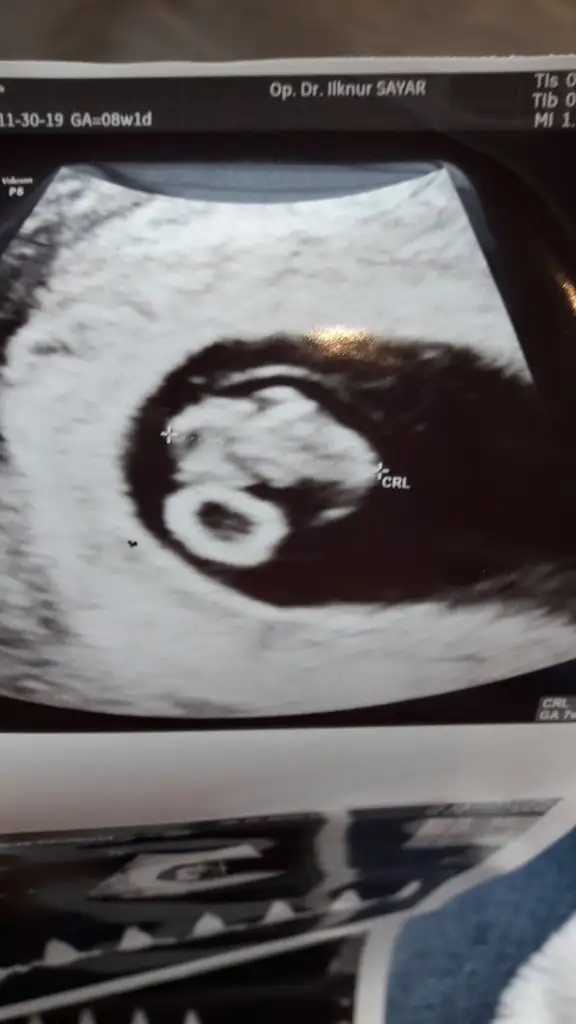

Cinsiyet tahmini yapabilen var mı aranızda çok merak ediyoruz 🥰